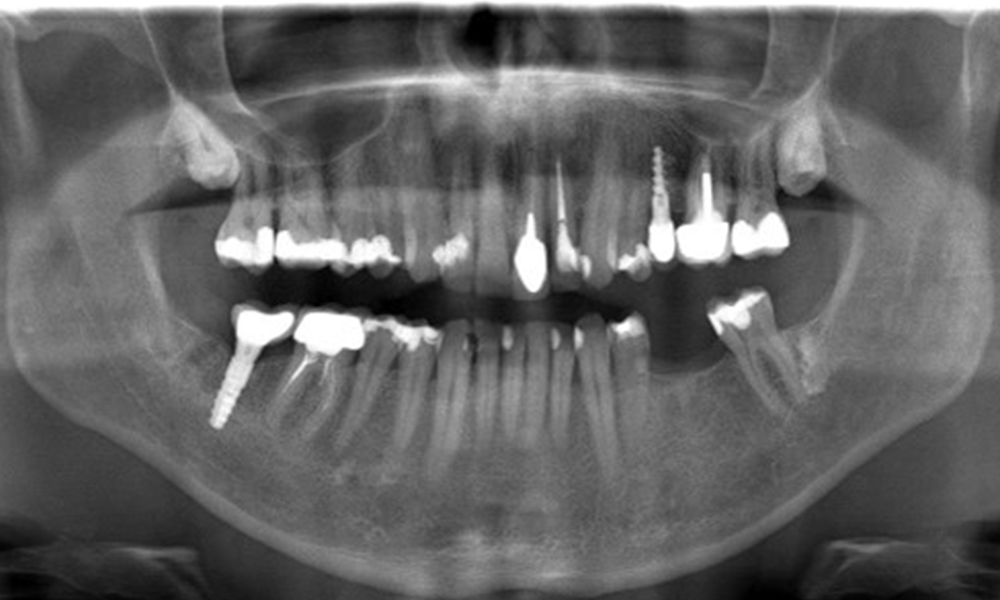

In the medical history, the 55-year-old patient states that he has no systemic disease and is not taking any medication. The patient’s lifestyle is similarly unremarkable. The patient has a few tooth restorations and two implants (2nd and 4th quadrants). On the basis of current findings, gingivitis is identified in an otherwise stable periodontal condition on the reduced periodontium (stage III, grade A).

Previous treatments: dental restorations (non-precious metal/ceramic blend), two implants (2nd, 4th quadrants)

Risk of onset: moderate for peri-implantitis

The patient has no particular risk factors with specific dental implications. The key factor, therefore, is the requirement in terms of oral health. In this respect, good oral health is evident with stable, reduced periodontium. Should evidence of an increase in probe depth compared with the baseline, combined with diffuse bleeding, be found at a check-up appointment, diagnosis using X-ray imaging (dental X-ray) should be undertaken in order to identify peri-implant bone loss at an early stage and intervene accordingly.